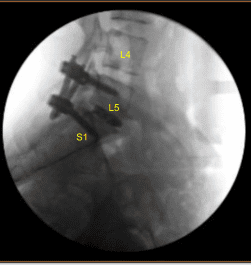

C-arm unit was brought into the field and sequential dilators were used to dock the tubular retractor over the left L5-S1 facet joints. Tubular retractor was affixed rigidly to the bed frame with the adaptor arm. Operative microscope was balanced, draped sterilely and brought into the field.

Morselized autograft selected during the decompression as well as morselized allograft was funneled into the interspace with funnel and tamp and then titanium interbody spacer was gently tamped into the interspace under fluoroscopic guidance and expanded into proper position. AP and lateral fluoroscopy showed appropriate positioning.

Next, additional CT scan was obtained showing slightly medial position of the left L5 guidewire. Therefore, Jamshidi navigation was again used to re-cannulate the left L5 pedicle into optimal position. the cannulated navigated pedicle screws were placed over the K wires and K wires were removed with at left L5 and S1 accomplishing a non segmental instrumentation.